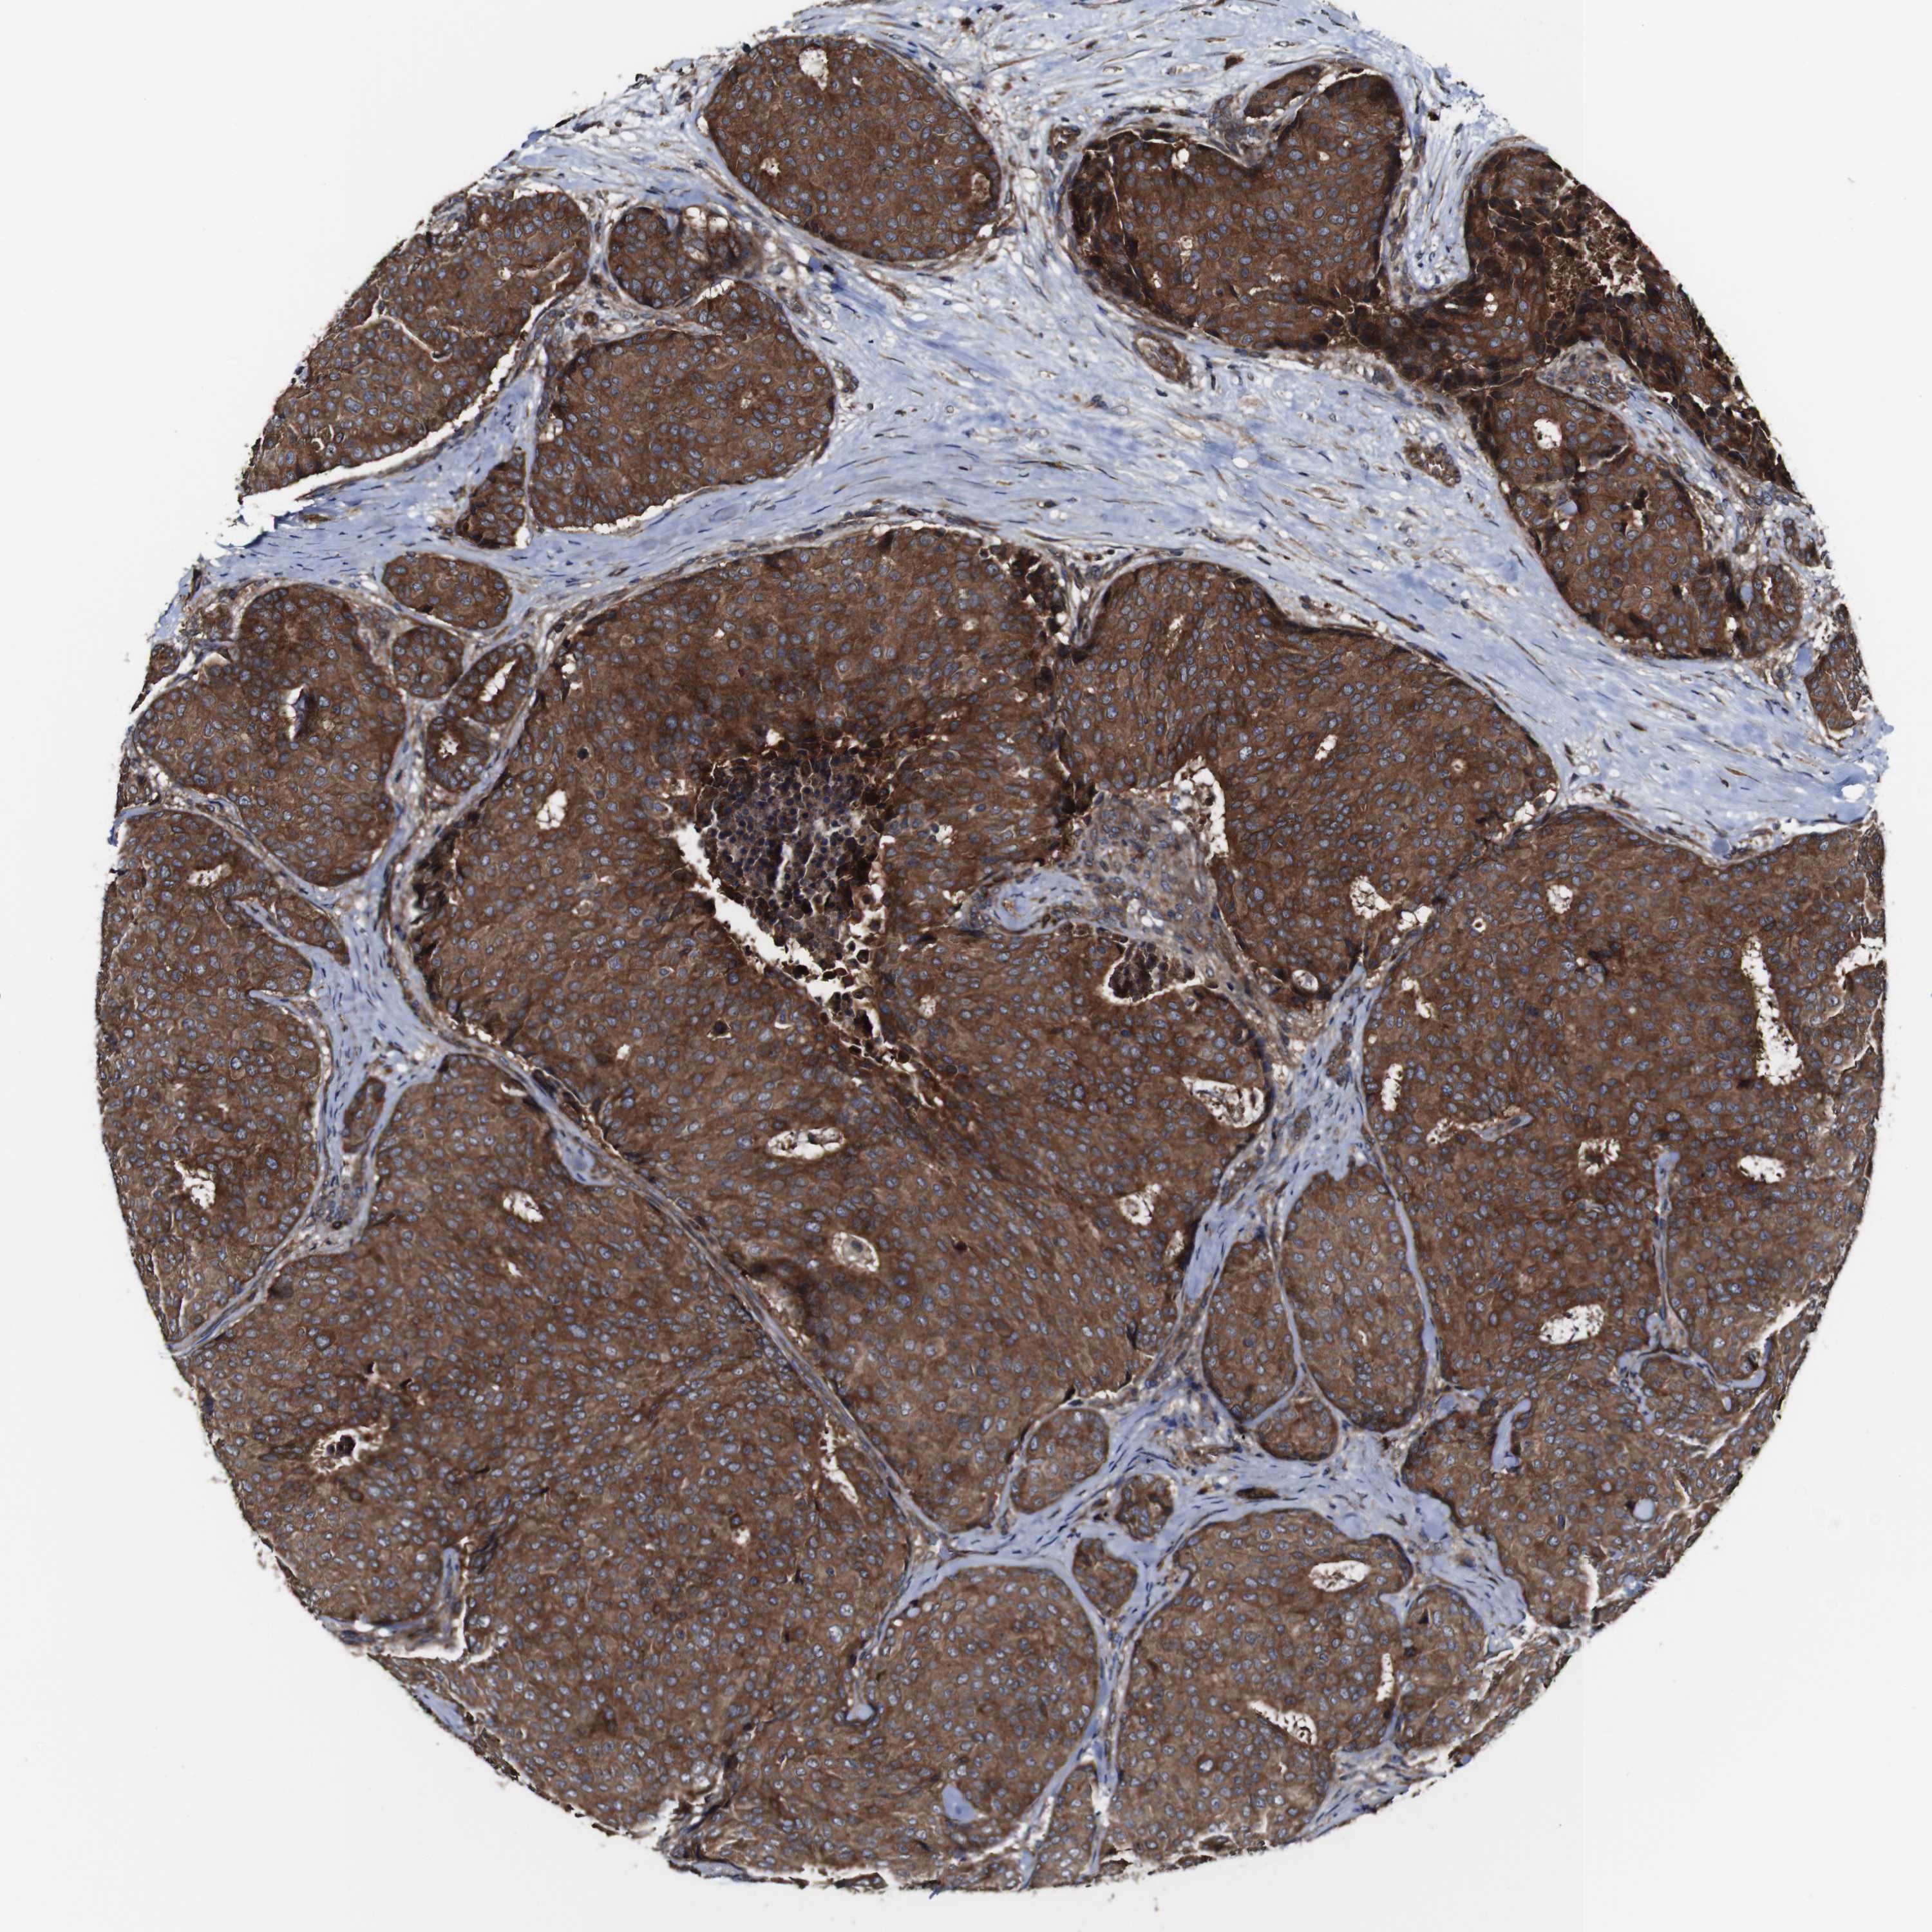

CANCER BREAST CANCER Show tissue menu

BRCA TCGA BRCA VALIDATION PROTEIN EXPRESSION